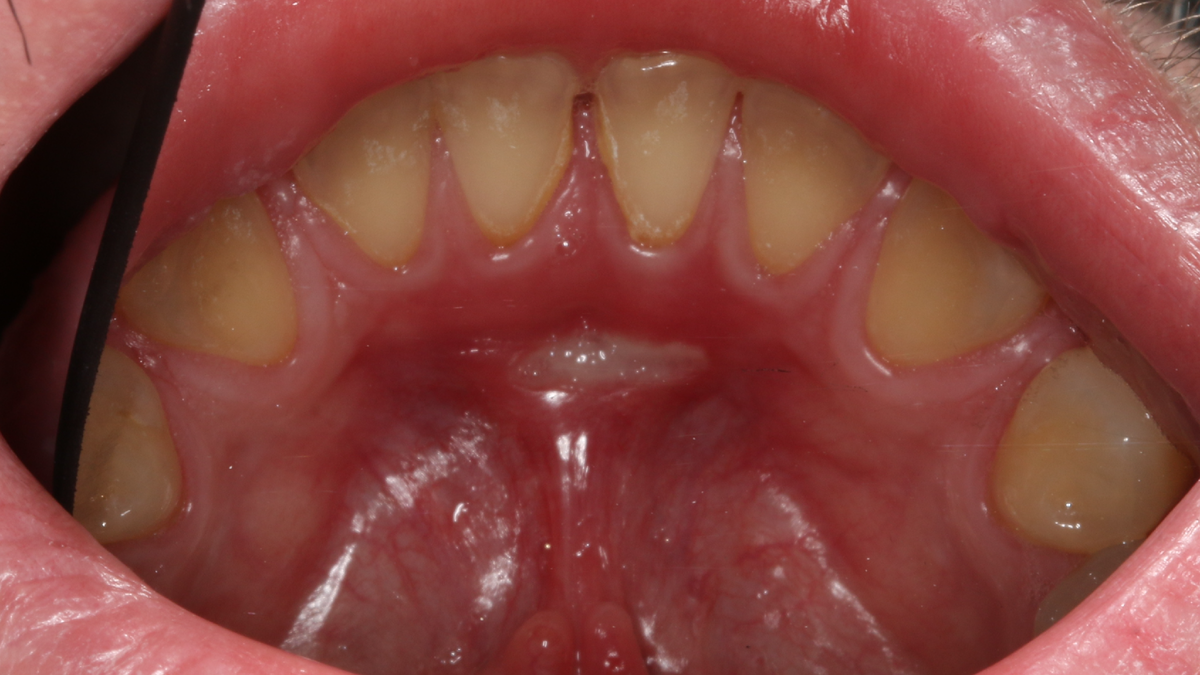

Травма уздечки языка чипсами. Заболело через 3 дня. В центре фотографии – типичная афта.

Поврежденное место выглядит опухшим, с покраснением слизистой оболочки. При контакте возникает боль. В центре припухлости – неглубокий очаг серовато-желтого цвета, обычно от 2 до 5 мм. Эта болячка – афта, потому и болезнь – афтозный стоматит (то есть воспаление слизистой оболочки с наличием афты).